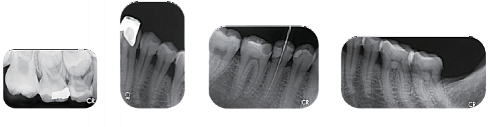

Визуализация выполняется быстро и просто. Кладёте пластину в отверстие сверху сканера и через короткое время на экране компьютера появляется чистая рентгенограмма, готовая к просмотру, редактированию и печати. Таким образом, различные анатомические структуры зуба: кость, корни, пульпа - отображаются на экране с высокой точностью.

Визуализация с помощью фосфорных пластин снижает время на диагностику и лечение пациента.